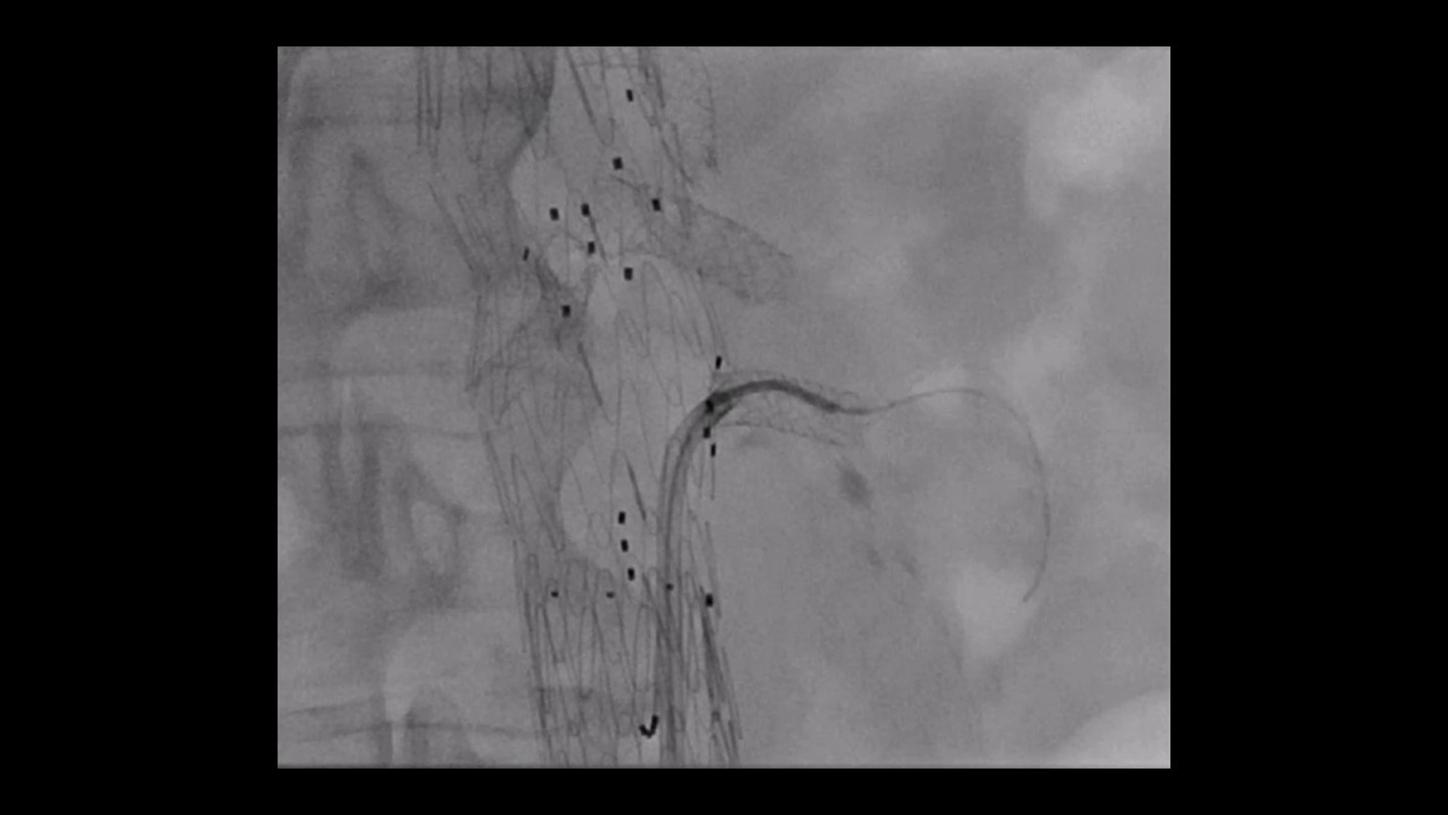

During minimally invasive procedures, it is critical to have a clear view of anatomies and devices. Yet complex imaging tasks or challenging patient conditions often impact image quality. OPTIQ AI delivers constant image quality1 defined by CNR in support of the ALARA principle, independent of patient or C-arm angulation. On top, an AI-powered algorithm reduces image noise in real time across different 2D imaging modes.

Make AI-powered imaging and clear insights your standard during interventions – with OPTIQ AI.

Future-focused IR imaging for a broad procedure mix

Discover how leading clinicians are transforming interventional radiology with Siemens Healthineers technologies. From ultra-fast 3D imaging to laser-guided needle procedures, the ARTIS icono ceiling powered by OPTIQ and syngo DynaCT are redefining what’s possible in IR. Explore real-world cases, expert insights, and the future of image-guided therapy.